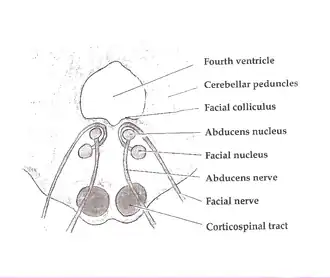

Scheme showing central connections of the optic nerves and optic tracts. Cross section of the pons at the level of the facial colliculus. PPRF is not labeled, but is visible adjacent to the abducens nucleus

Cross section of the pons at the level of the facial colliculus. PPRF is not labeled, but is visible adjacent to the abducens nucleus